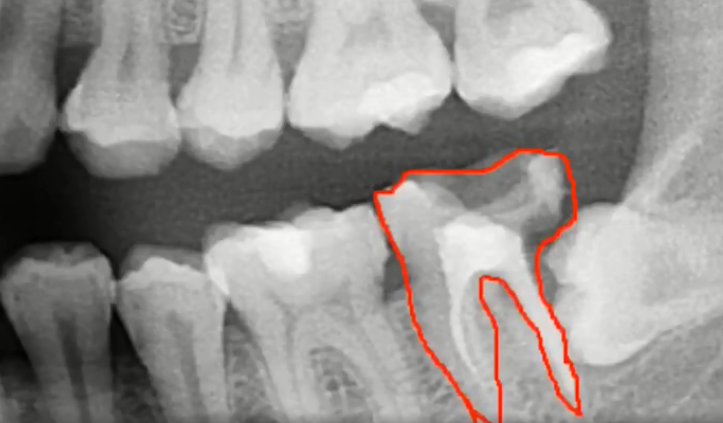

第二磨牙壞掉嚴(yan) 重選擇拔除,把智齒牽引出來頂替

如果智齒對牙齒矯正沒有影響,甚至可以把埋伏長歪的智齒牽引出來,頂替懷掉或者缺失的第二磨牙,這是智齒“廢物利用”的表現,需要綜合評估確定。

正畸把智齒成功牽引出來